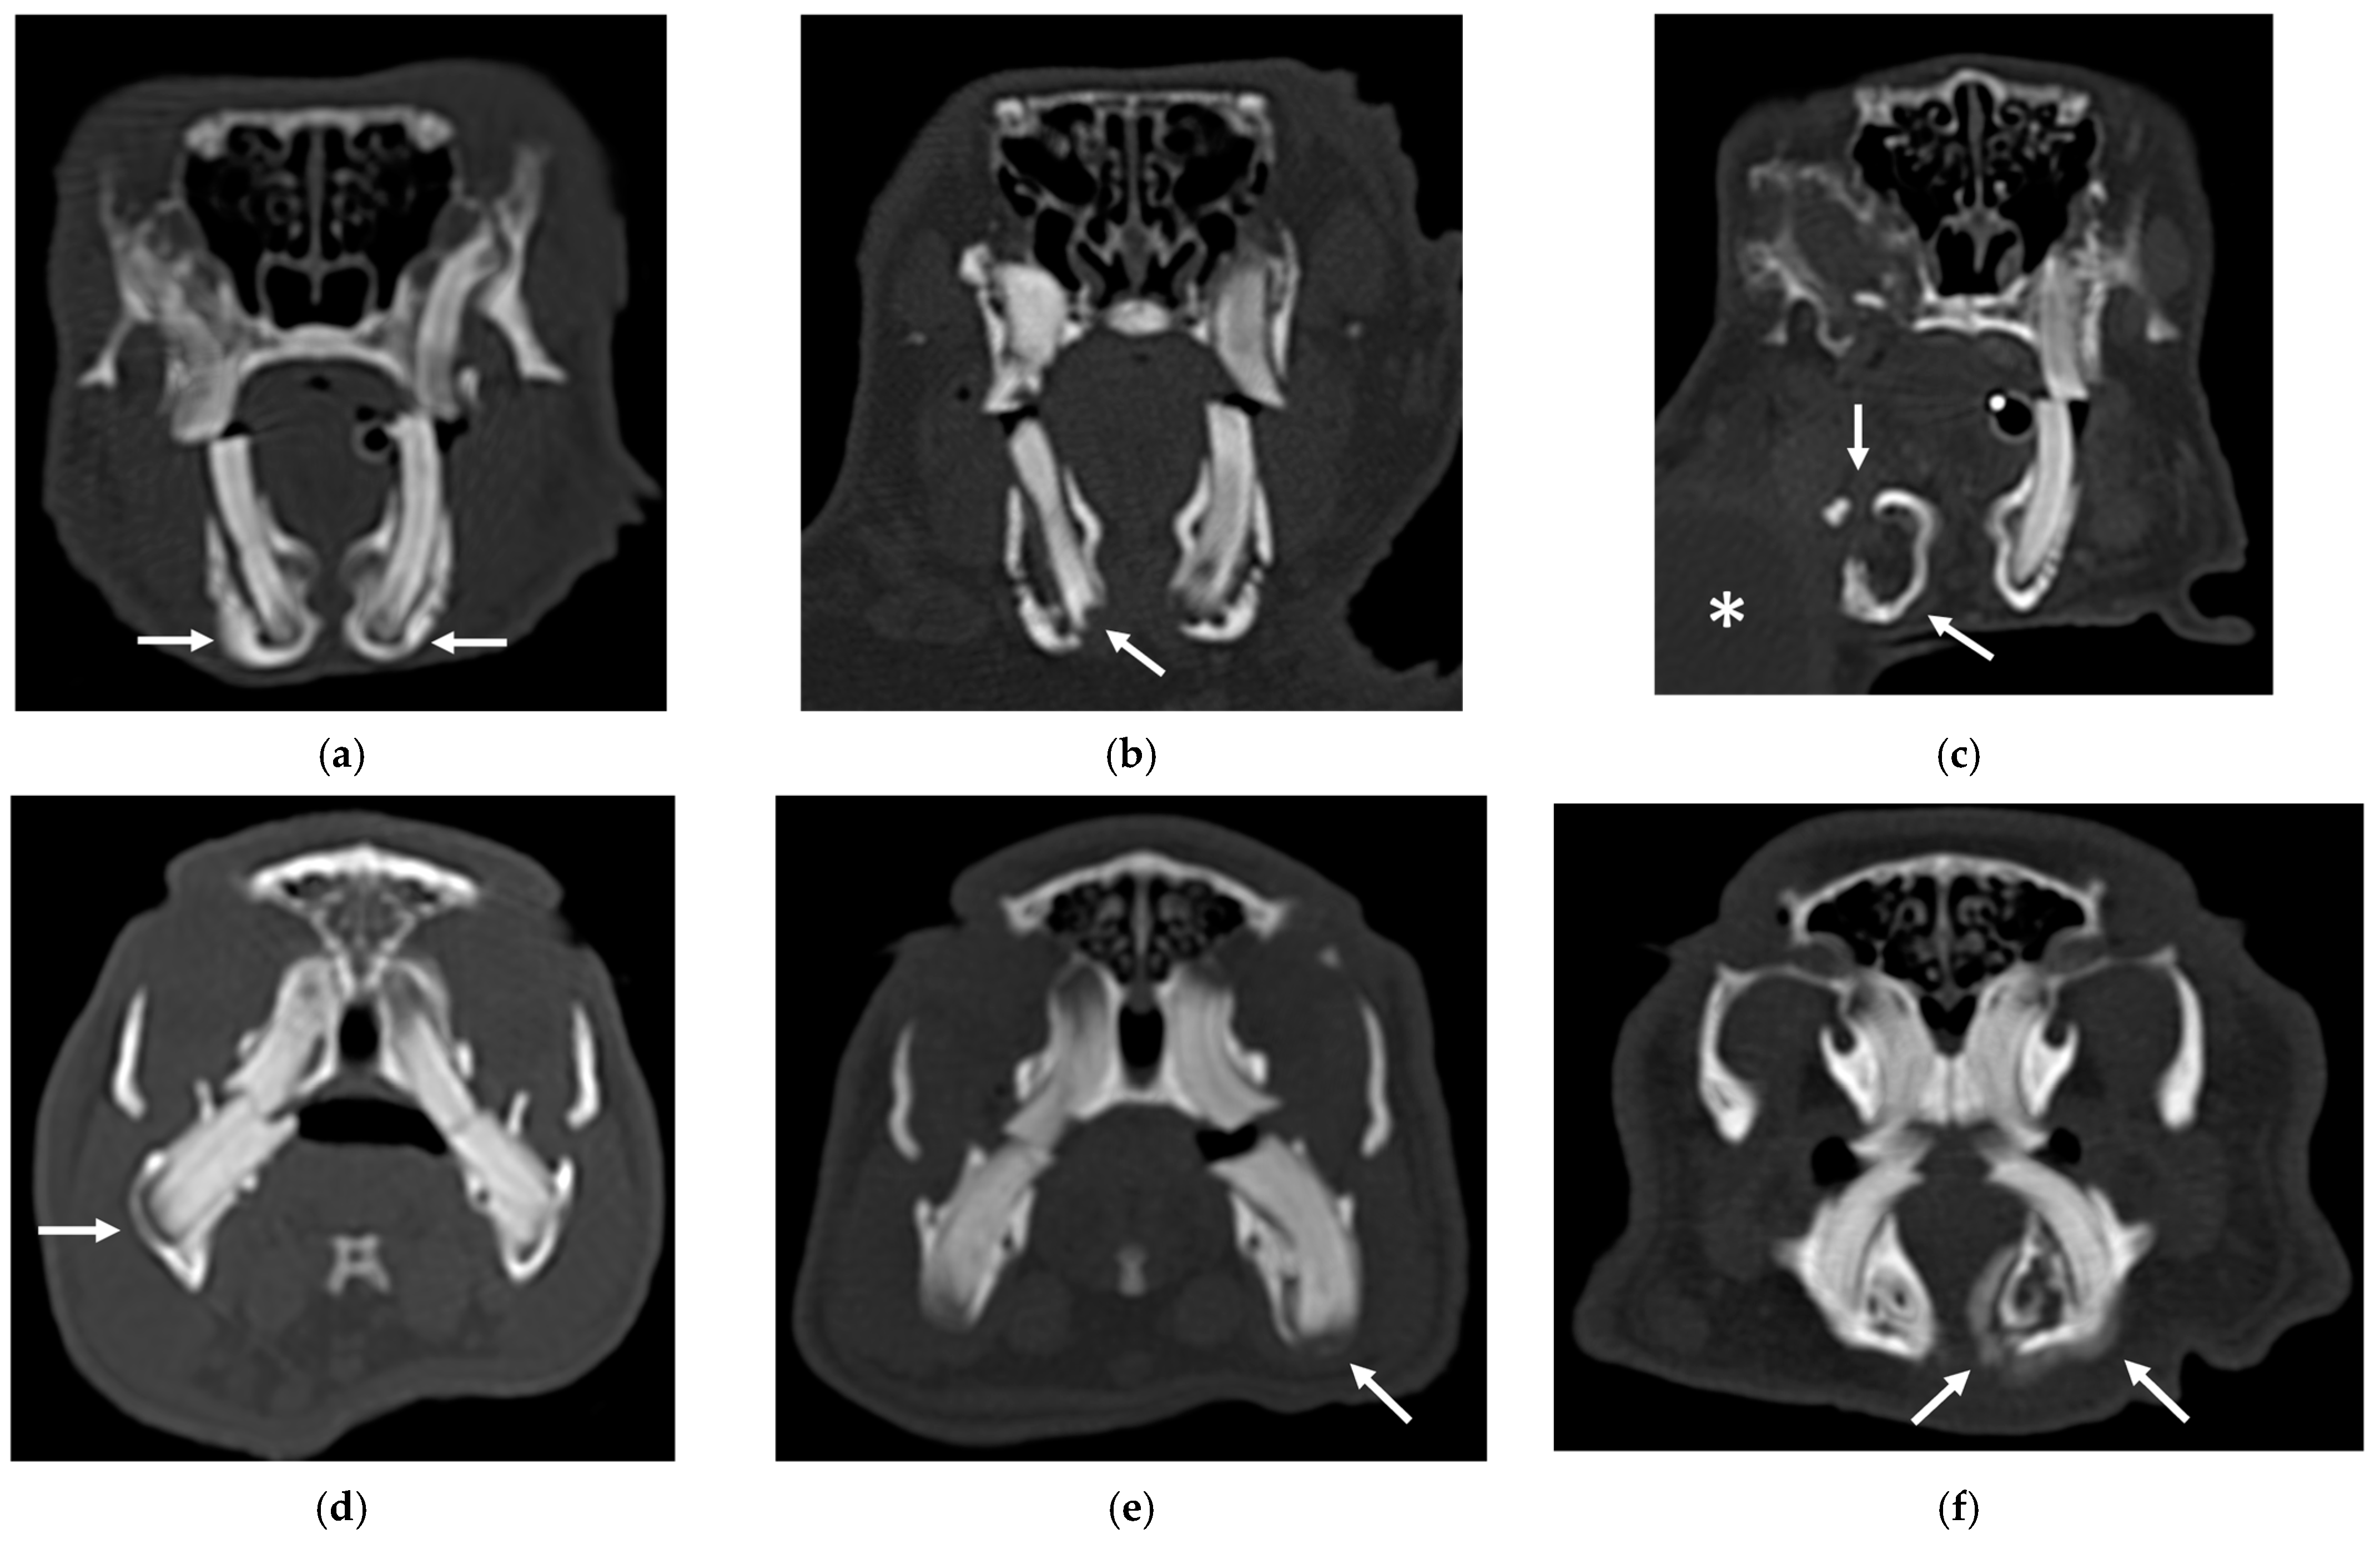

An example of the three categories of secondary bone lesions is shown for a rabbit and a guinea pig in Figure 2.

Figure 2.

Transverse CT images of mandibular secondary bone lesions of three rabbits (a–c) and three guinea pigs (d–f) included in the study; bone algorithm. (a,d) Bulging around tooth without focal lysis (white arrows); (b,e) bulging around tooth with focal lysis (white arrow); (c,f) aggressive bone lesion associated with teeth (white arrow). Note the associated cavernous occupying lesion of soft tissues (white asterisk) in image (c).

The IT were more frequently involved in guinea pigs with aggressive bone lesions associated with teeth (3). In the second group of patients, variable involvement of different groups of teeth was observed. The involvement of the premolar and molar teeth presented variable distribution in both species in all three categories of secondary bone lesions. Only three rabbits and three guinea pigs exhibited involvement of IPMT, associated with aggressive bone lesion associated with teeth (3) in rabbits, and bulging around tooth root with focal lysis (2) and aggressive bone lesion associated with teeth (3) in guinea pigs, respectively, in two and one patients.